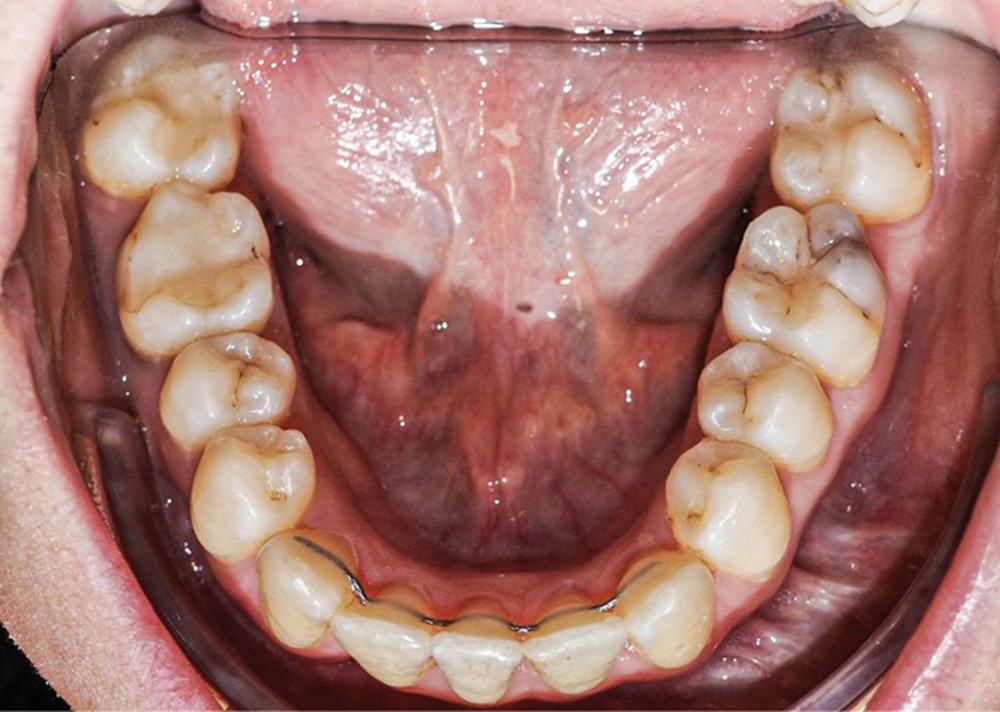

Examen endo-buccal (fig. 2a-e)

L’arcade maxillaire est parabolique, la 12 présente une légère mésio-rotation. L’arcade mandibulaire est également parabolique avec un encombrement antérieur estimé à 6 mm. On note une dyschromie de la 31, dont le test de vitalité est négatif. Le parodonte est fin.

En occlusion, on note une relation de Classe I molaire bilatérale avec un surplomb normal et une supraclusion. Les médianes incisives sont concordantes.

Les incisives maxillaires sont de forme triangulaire [1] et l’indice de Bolton est de 97 % qui traduit la présence d’une DDD par excès mandibulaire.